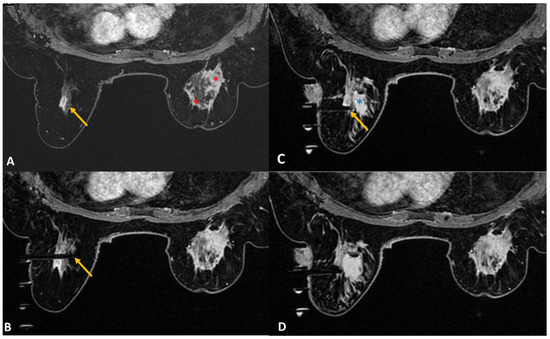

Figure 9.

(A). In a patient with recently diagnosed right breast cancer (red asterisks), staging MRI showed a 9-mm enhancing mass (yellow arrow) in the left breast at 12 o’clock. (B). During biopsy, the tip of the obturator was seen beyond the target (yellow arrow). This was because the wrong needle size was mistakenly selected on CAD software producing wrong ‘z’ axis/depth. (C). The obturator depth was then adjusted to correct depth with its tip at the lesion (yellow arrow). By this time, a significant size of hematoma (blue asterisk) was noted in the inner half of the breast from arterial injury. (D). The biopsy of the target was completed successfully and the histology from the left breast lesion was reported as high-grade DCIS with comedonecrosis.